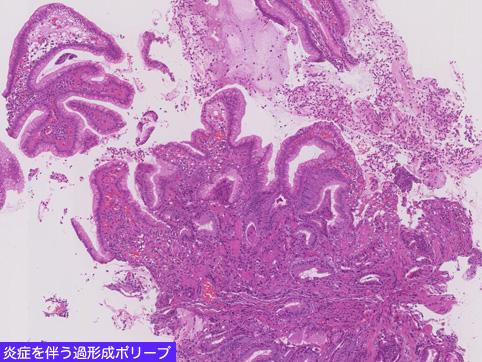

疾病(病理主体)的分类肿瘤样病变/组织增生性息肉

检查方法病理切片(微观)

肿瘤最大直径10~14